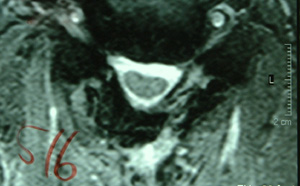

| MRI画像(東京女子医科大学整形外科提供) | ||

| 手術前 | 手術後 | |

| 縦断面(中心) | ![]() |

![]() |

| 所見 | 頸椎ジョイント部で狭窄が顕著。脊髄と脊柱管の間の余裕がない。部分的に、脊髄内部に血行障害が認められる。 | 脊柱管は拡大され脊髄は自由に位置している。脊髄と脊柱管の間の余裕も確保されている。 |